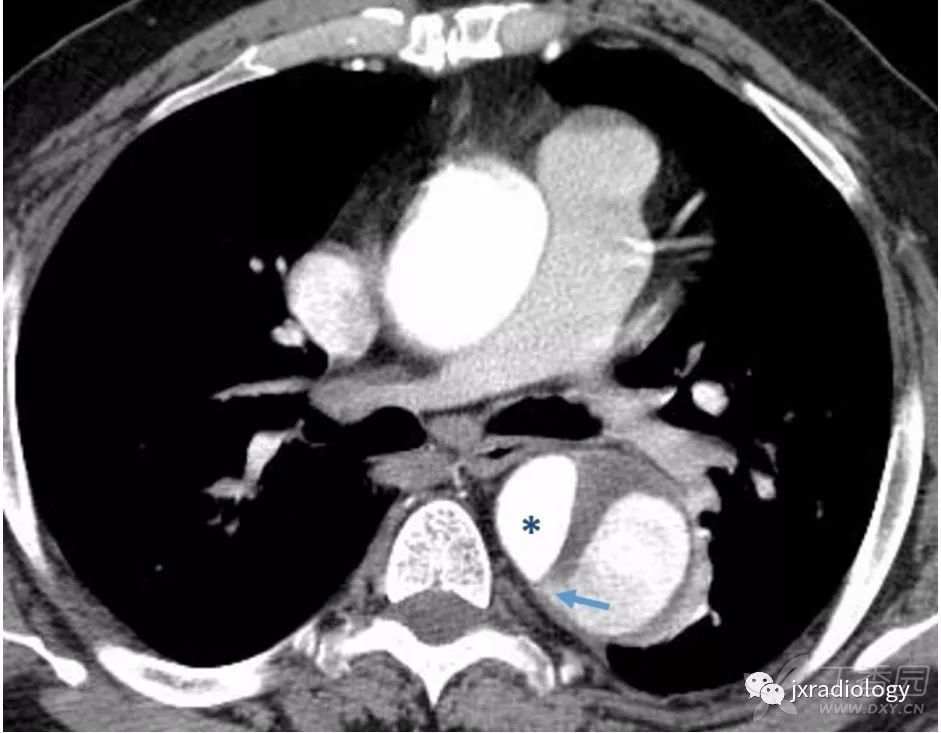

主动脉夹层的一个重要的并发症是分支阻塞,可以是静态的或动态的。在第一种静态阻塞机制中,内膜瓣进入分支血管起始部而没有再延伸( 图3 )。这导致这个分支的压力上升和血栓形成,引起局部血管狭窄及器官缺血。

动态阻塞是指当撕裂内膜像窗帘一样覆盖主动脉的一个分支;也可导致局部缺血( 图4 )。

图4:A型主动脉夹层患者的对比增强CT。

在矢状MIP(a)中,可见真腔位于前面,假腔占据大部分主动脉直径。内膜钙化有助于识别真腔。从真腔(a图和c图)看来,即使腹腔干起源于真腔,假腔的压力增加会导致内膜向前移位,压迫真腔并阻塞腹腔干的开口(c图)。肠系膜上动脉(a图)的开口处可见相同的机制。